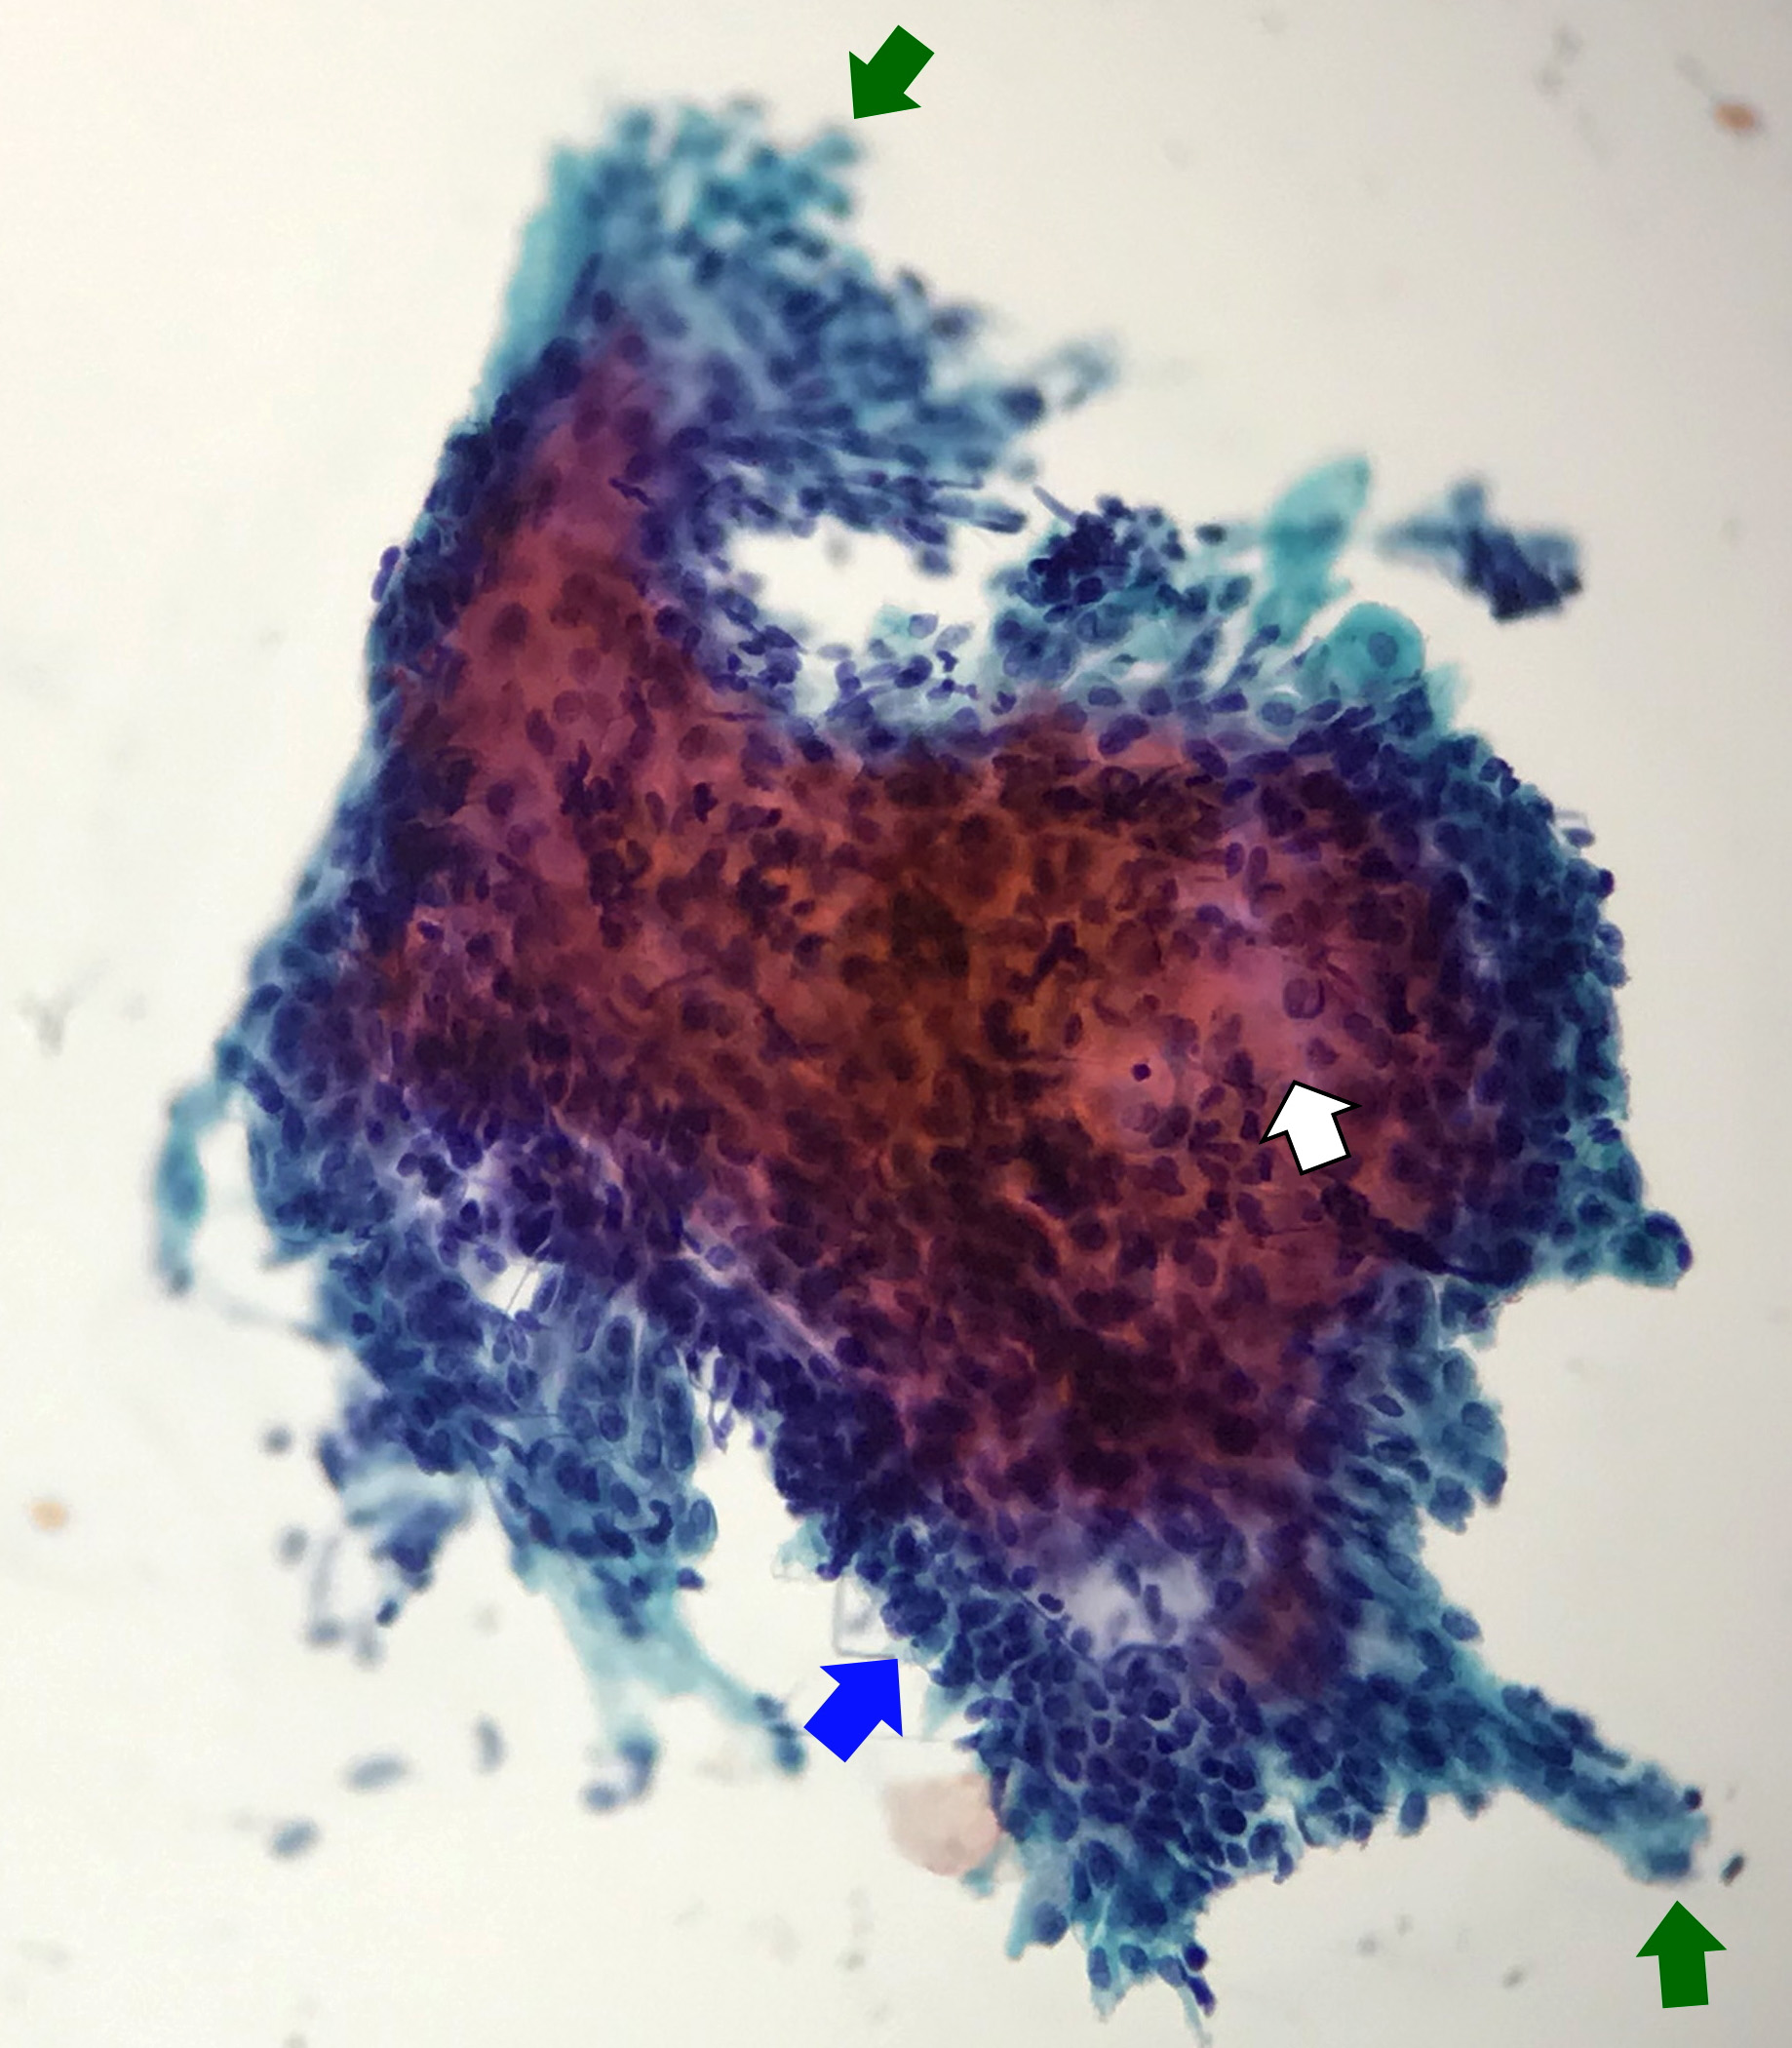

Cytology description

- Compact and cohesive cell clusters with areas of short branching of tumor cells along the periphery (Diagn Cytopathol 2013;41:206)

- Oval to round basaloid cells with high nuclear to cytoplasmic ratios, fine powdery chromatin, nucleoli with small peripheral nucleoli to inconspicuous nucleoli

- Squamous cells centrally with more abundant cytoplasm (particularly in acanthomatous variant)

- Possible limitations to FNA

- Inadequate sampling due to extensive cyst formation within the tumor

- Inability to distinguish ameloblastoma with macrocystic degeneration from ameloblastoma, unicystic type

- Inability to distinguish ameloblastoma from metastatic ameloblastoma without prior knowledge of metastatic disease

- Inability to distinguish ameloblastoma from other benign odontogenic tumors that are managed with curettage (e.g. adenomatoid odontogenic tumor, ameloblastic fibroma) (Diagn Cytopathol 2013;41:206)